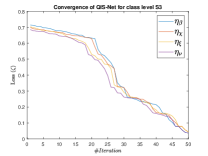

The suitable tailoring of the phase angle in the Hadamard gate advocates the stability of the QFS-Net or its convergence which is very crucial for self-supervised networks where the loss function (here error function) is dependent on the interconnection weights. Hence, the phase angles are evaluated using and as given in Equations 18 and 21, respectively. It is worth noting that the qutrit based quantum neural network provides faster convergence compared to the classical neural networks. This is due to the fact that whereas the classical neural networks are formed using the multiplication of input vector and the weight vector guided by an activation function, the quantum-based networks incorporate the frequency components of the weights and their inputs thereby enabling faster convergence of the network states. This inherent novel feature of the quantum neural networks facilitates the qutrit based fully self-organized quantum algorithm to be employed in QFS-Net to converge super-linearly, as shown in Figure 3. The loss function cum QFS-Net network error function is defined on quantum measurement in the following way.

| (37) |

where, represents the true interconnection weight terms of the inter-connection weights as expressed using the Hadamard gate () at an instance (). is a coherent error function of and . Convergence analysis of the proposed qutrit-inspired QFS-Net is provided in Appendix Section -A and demonstrated experimentally with qubit embedded QIS-Net [39] as shown in Figure 3. It can be summarized that the convergence of the QFS-Net is faster than that of the QIS-Net and also follows super-linearity. This claim is also substantiated by the number of iterations required to converge for each image slice in QFS-Net and QIS-Net as illustrated in Figure 4.